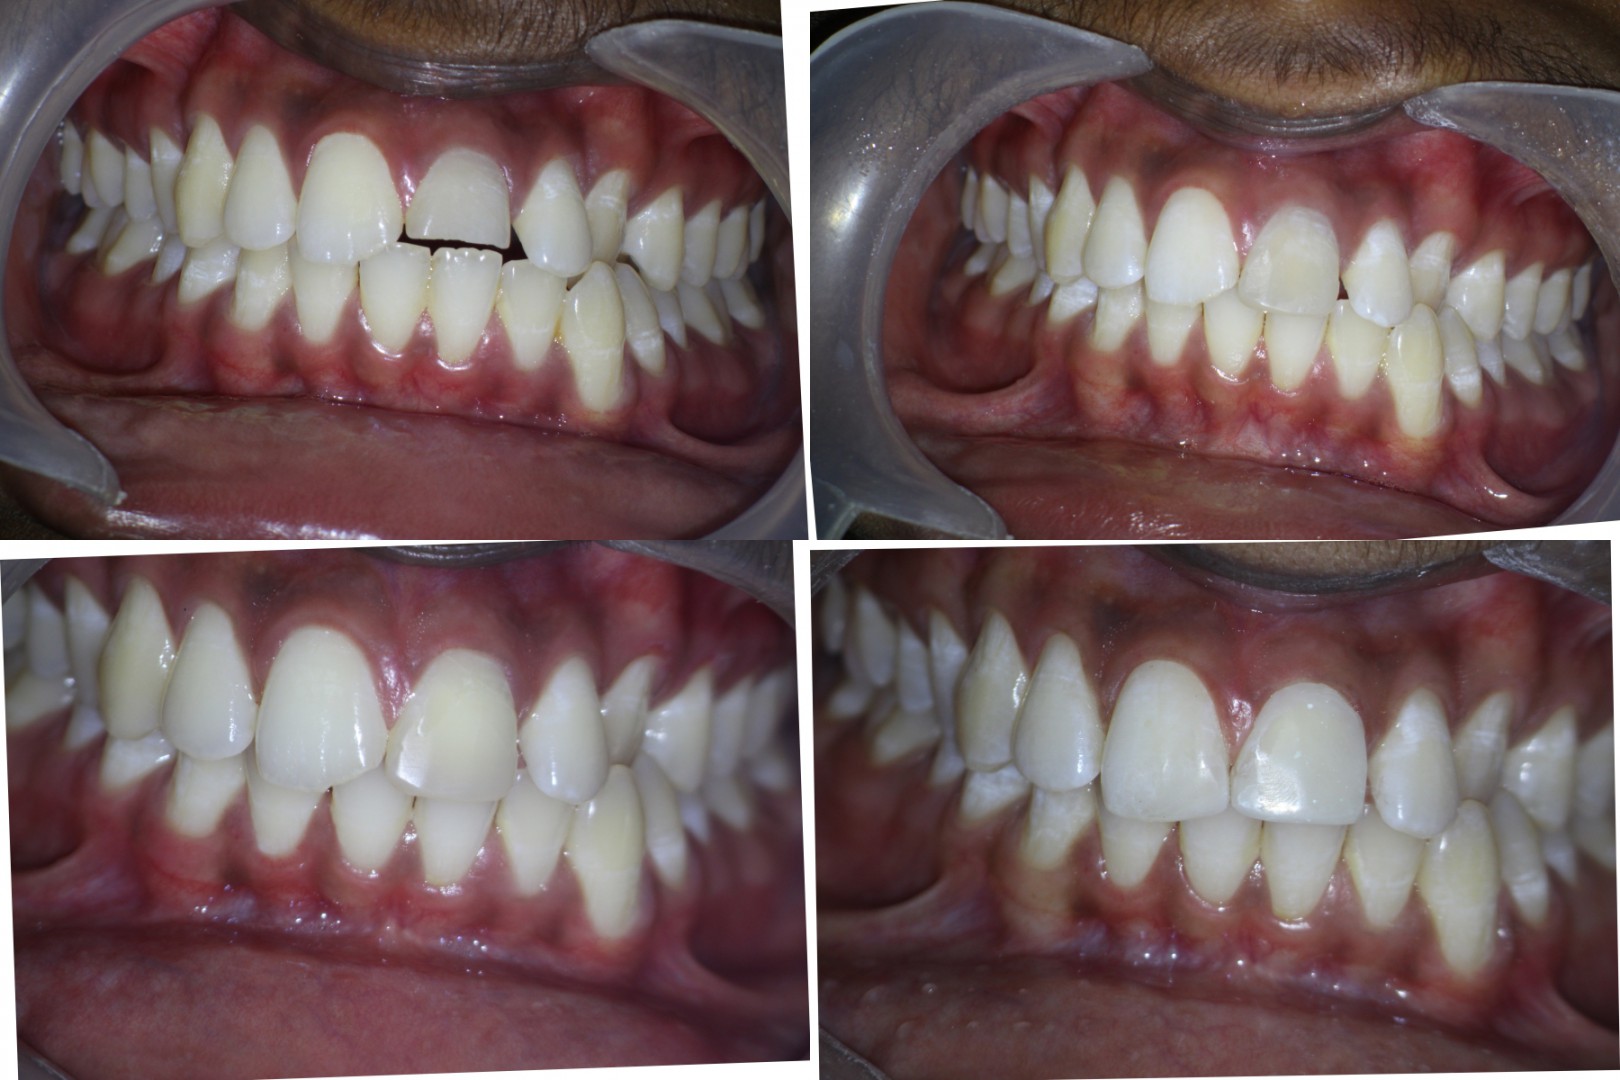

Pt 17yrs male presented with pain and discoloration of #9. After the Access prep,cleaning and shaping , temporary composite restoration was done. After 2 visits of CAOH dressing obutration completed and bleach placed for a week. Composite resoration done in #8 and repeated in #9.

Nice management! The patient must have been excited to have his tooth back to normal. How long ago had the trauma occurred?

Yes, both the patient and parents were happy.

Trauma happened 3 yrs back.

Wow, long time for a kid to have a broken tooth. Again, nice case!